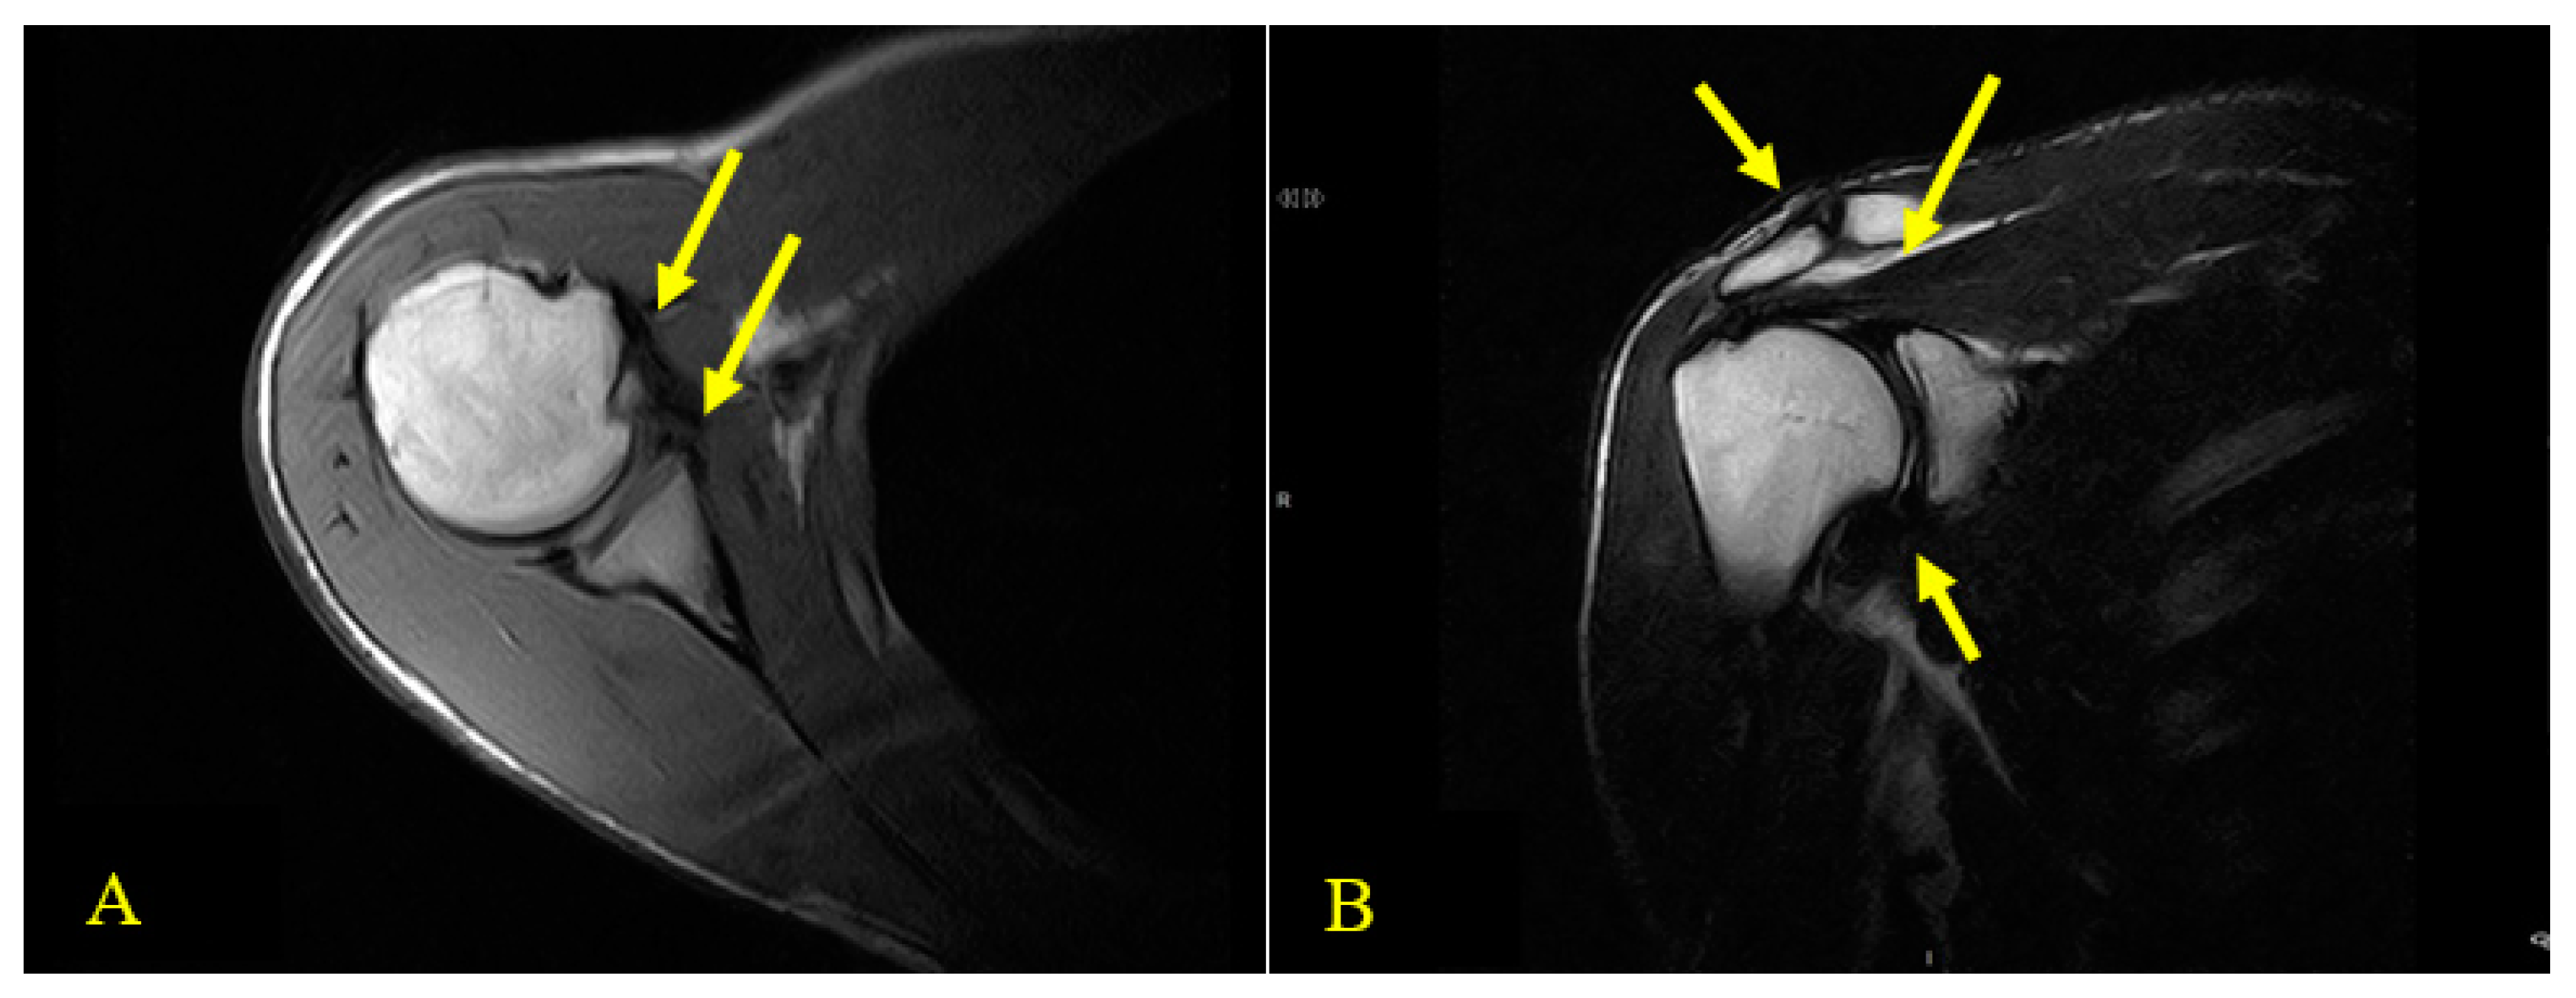

After a fall during a cycling race, the athlete went to a medical clinic in March 2017 and was diagnosed with subsequent dislocations of the right shoulder. The fall occurred following contact with a teammate during an international championship while riding on a paved road. The patient was not able to describe the exact traumatic mechanism but remembers his attempt to place his hands toward the ground to avoid the collision. The diagnostic investigation at the time, a magnetic resonance image (MRI), signaled the presence of “intra-articular effusion with non-homogeneity of the antero-inferior portion of the glenoid rim, bone marrow edema on the anterior surface of the humeral head, and an extensive lesion of the subscapularis tendon” (Figure 1). The anamnestic examination was highlighted by a numeric pain rating scale (NPRS) [18] of 6/10 (while the patient was at rest), widespread tenderness on the entire joint complex, and positive clinical tests (posterior drawer test, sulcus sign, load and shift, and apprehension test). The patient did not report further trauma to the joint until May 2018, when, during normal work activities (while lifting a box onto a shelf that was above shoulder height), the patient experienced another posterior dislocation of his right shoulder. After this dislocation, the number of episodes of dislocation during limb movements in normal daily activities of living increased in frequency and intensity. Subsequently, spasms of the joint complex followed these episodes and became more frequent with multiple spontaneous and multidirectional dislocations of the shoulder (Video S2).

Figure 1.

(A) and (B) Axial and coronal views of T1-weighted magnetic resonance imaging (MRI) scans. (A) Axial view of T1-weighted MRI. Two thick yellow arrows indicate inhomogeneity of the antero-inferior portion of the glenoid rim (bottom right), a McLaughlin lesion in the anterior aspect of the humeral head, and an extensive tear of the subscapularis tendon (top right). (B) Coronal view of T1-weighted MRI. Three thick yellow arrows indicate unevenness of the ACJ (top left), lesion of the pre-insertional bundles of the supraspinatus and fluid distension of the subacromial bursa (SAB) with diastasis of the glenoid bone (top right) and, slight thickening of the anterior capsule ligament (bottom right).